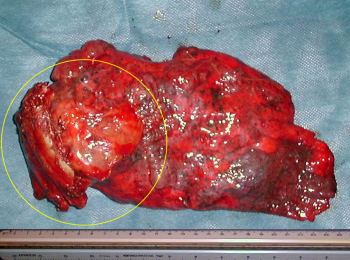

• Fotografia de la pieza resecada

•   Los segmentos lobares superiores y medios unidos por ausencia de cisura transversa, vistos por su cara externa toracica.

En circulo, la lesión sólida con el segmento de pared toracica, resecados en una sola pieza. "Resección en bloque".